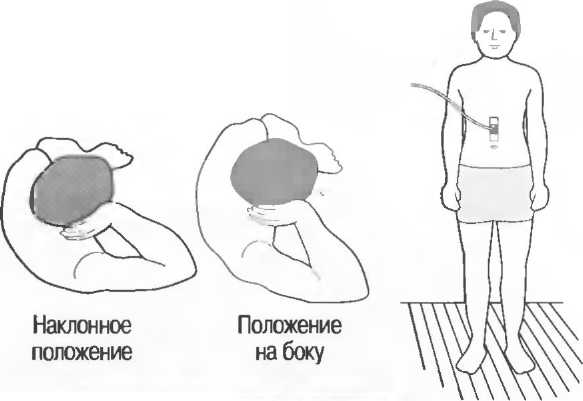

Если Вам не удается увидеть то, что требуется, необходимо повернуть пациента в другое положение: или развернуть его в полоборота (в наклонное положение), или провести исследование в положении больного стоя или в коленно-локтевом положении.